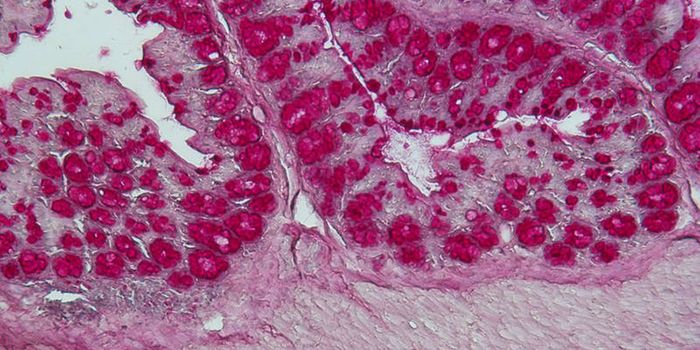

DEC 10, 2015ImmunologySuperior technology brings us novel images of cancer cells and lymphocytes this week, and now scientists can learn more ...